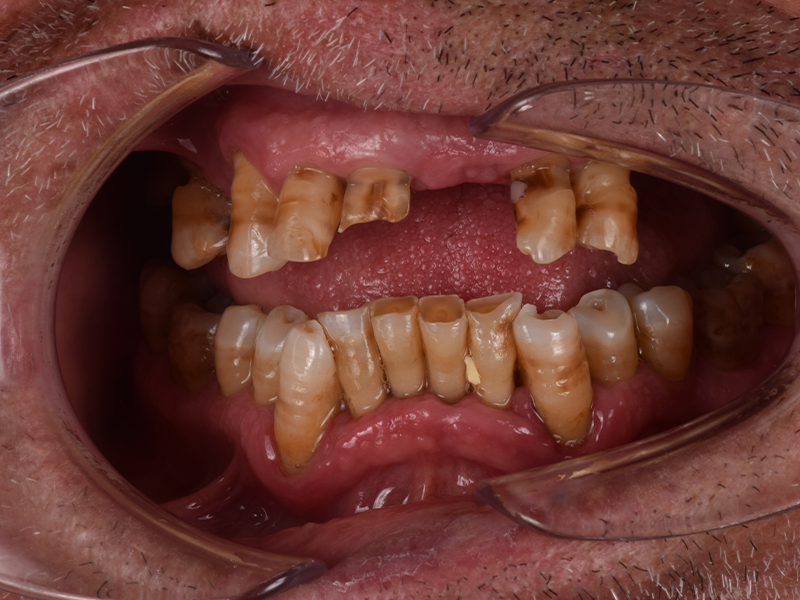

PRIMA